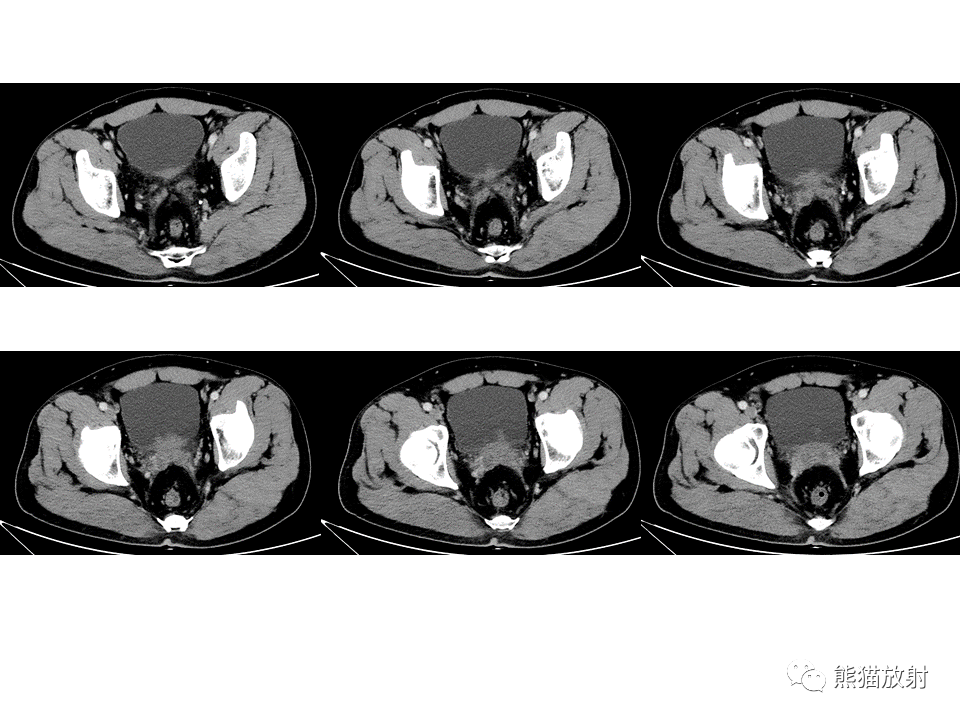

腺性膀胱炎与膀胱尿路上皮癌丨ct鉴别诊断科室交流学习资料内容由研究

图片尺寸960x720

术前膀胱肿瘤增强ct表现

图片尺寸1600x1200